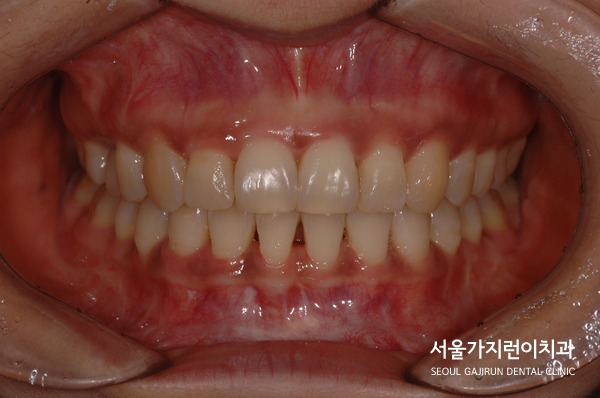

환자분의 경우 과개교합에 해당하셨는데요.

과개교합의 경우 윗니가 아랫니를 비정상적으로 덮고 있는 교합을 말합니다.

아랫니가 윗니를 덮는 경우는 주걱턱으로 많이 알고 있지만 반대의 경우 생각보다 많이 계신데요.

상악 앞니가 하악 앞니를 누르고 있었기 때문에 상당한 통증도 호소한 케이스였습니다.

환자분의 경우 상악 앞찌가 안쪽으로 기울어진 상태였다가 하악앞니는 덧니 소견도 있었는데요.

말끔하게 해결된 것을 확인할 수 있었습니다. 임플란트도 이상없이 안정적으로 유지된 것을 볼 수 있는데요.